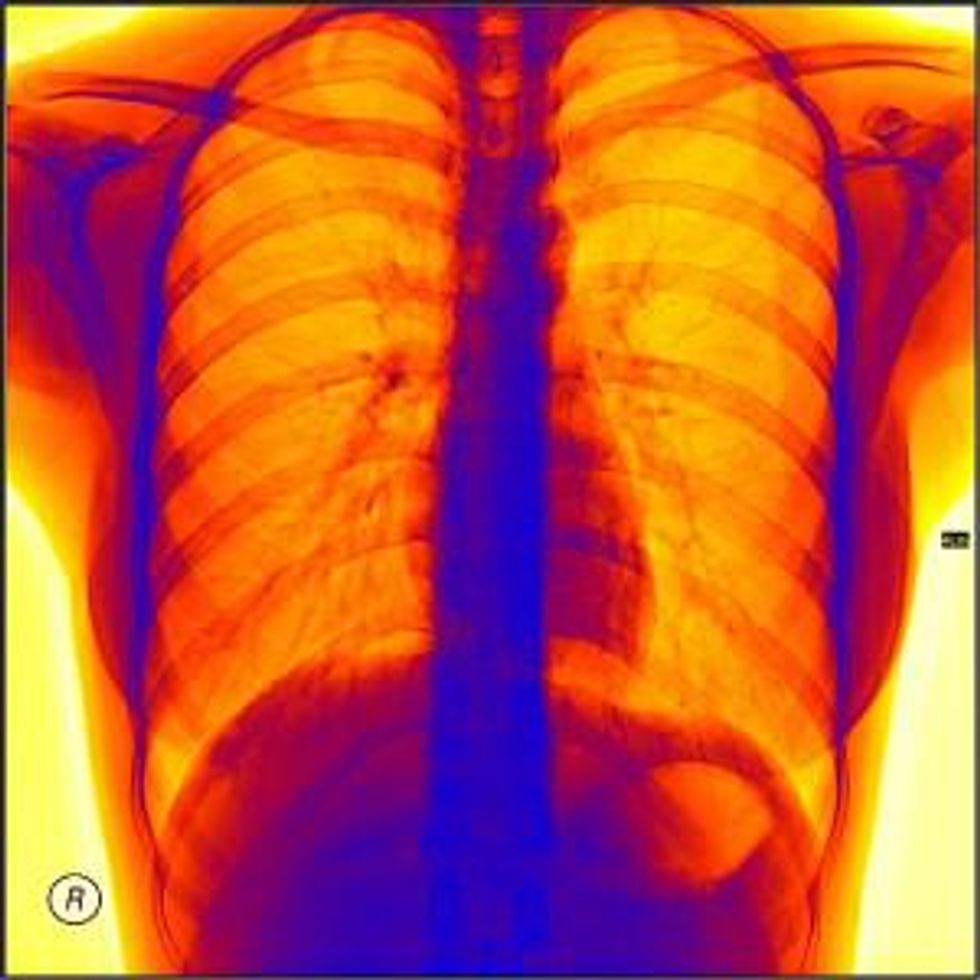

Global medical imaging market revenues are expected to grow from $24.1 billion in 2012 to nearly $30 billion by 2017, according to research from Frost & Sullivan’s 2013 global Medical Imaging Equipment Market Outlook Report. Medical imaging includes X-rays, magnetic resonance imaging (MRI), computed tomography (CT) scans, ultrasound and nuclear medicine.

Medical imaging tools are not only used in the proactive detection and treatment of diseases but also in clinical trials of pharmaceuticals. Technology in this market is growing rapidly alongside demand as modern medicine continues to emphasize early detection and minimally invasive procedures.